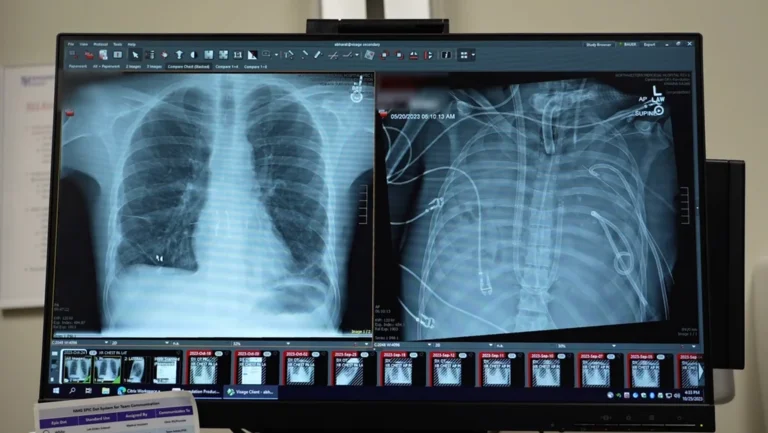

يومان بلا رئتين.. تقنية ثورية تنقذ مريضاً كان يحتضر

في سابقة طبية، تمكن جراحون من إبقاء رجل على قيد الحياة بصدر فارغ تماماً لمدة يومين باستخدام نظام رئة اصطناعية متطور، مما أتاح له فرصة النجاة من عدوى قاتلة وتلقي زراعة ناجحة.